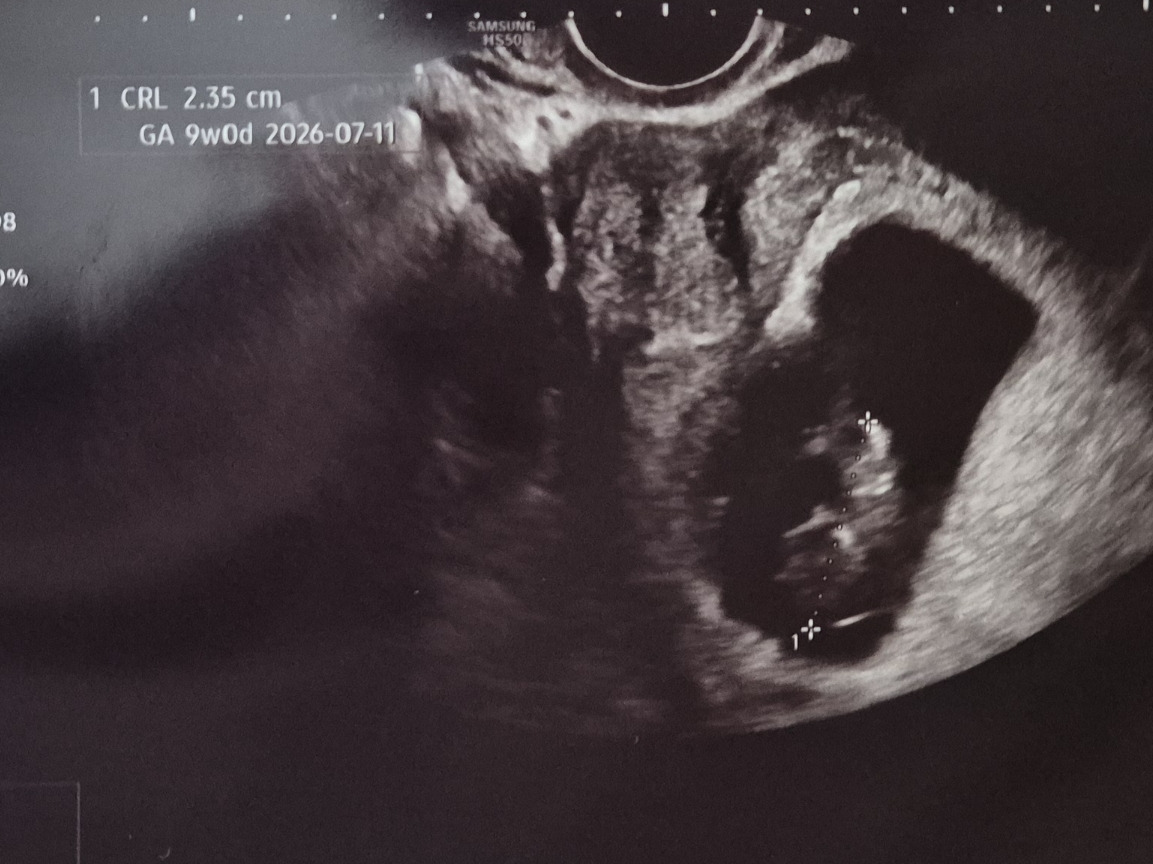

이제는 9주 차가 된 복복이

사랑해 복복아 엄마영양분 다 뺐어도 되니깐 제발 딱 붙어서 튼튼히 자라 가지고 건강하게 만나자

새로 전원 한 산부인과 원장님 설명도 꼼꼼하고 좋은데 초음파사진은 휘리릭 대충 찍어주시는 게 아쉽다..